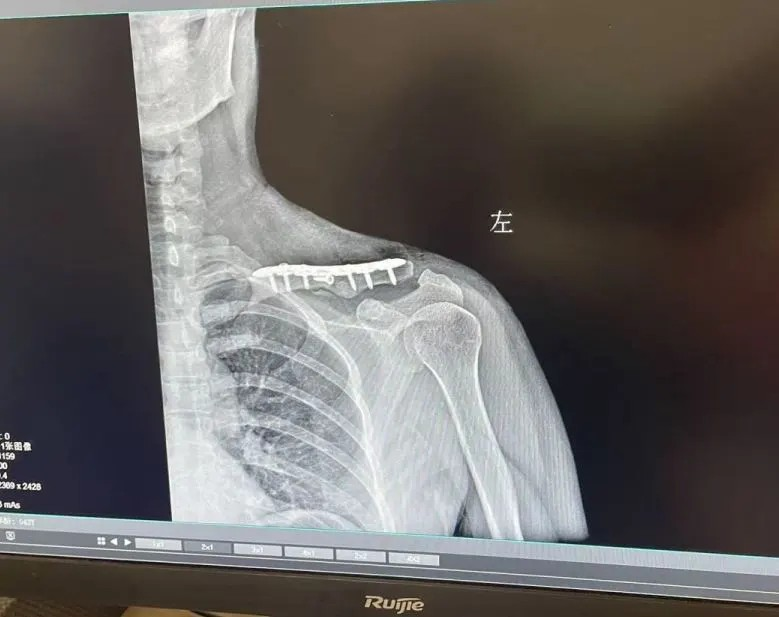

股骨头坏死晚期,此时股骨头完全塌陷,保留股骨头也没有意义了。此时多采取人工髋关节置换术,能快速缓解疼痛、恢复活动能力,目前手术技术成熟,假体寿命可达20年左右。